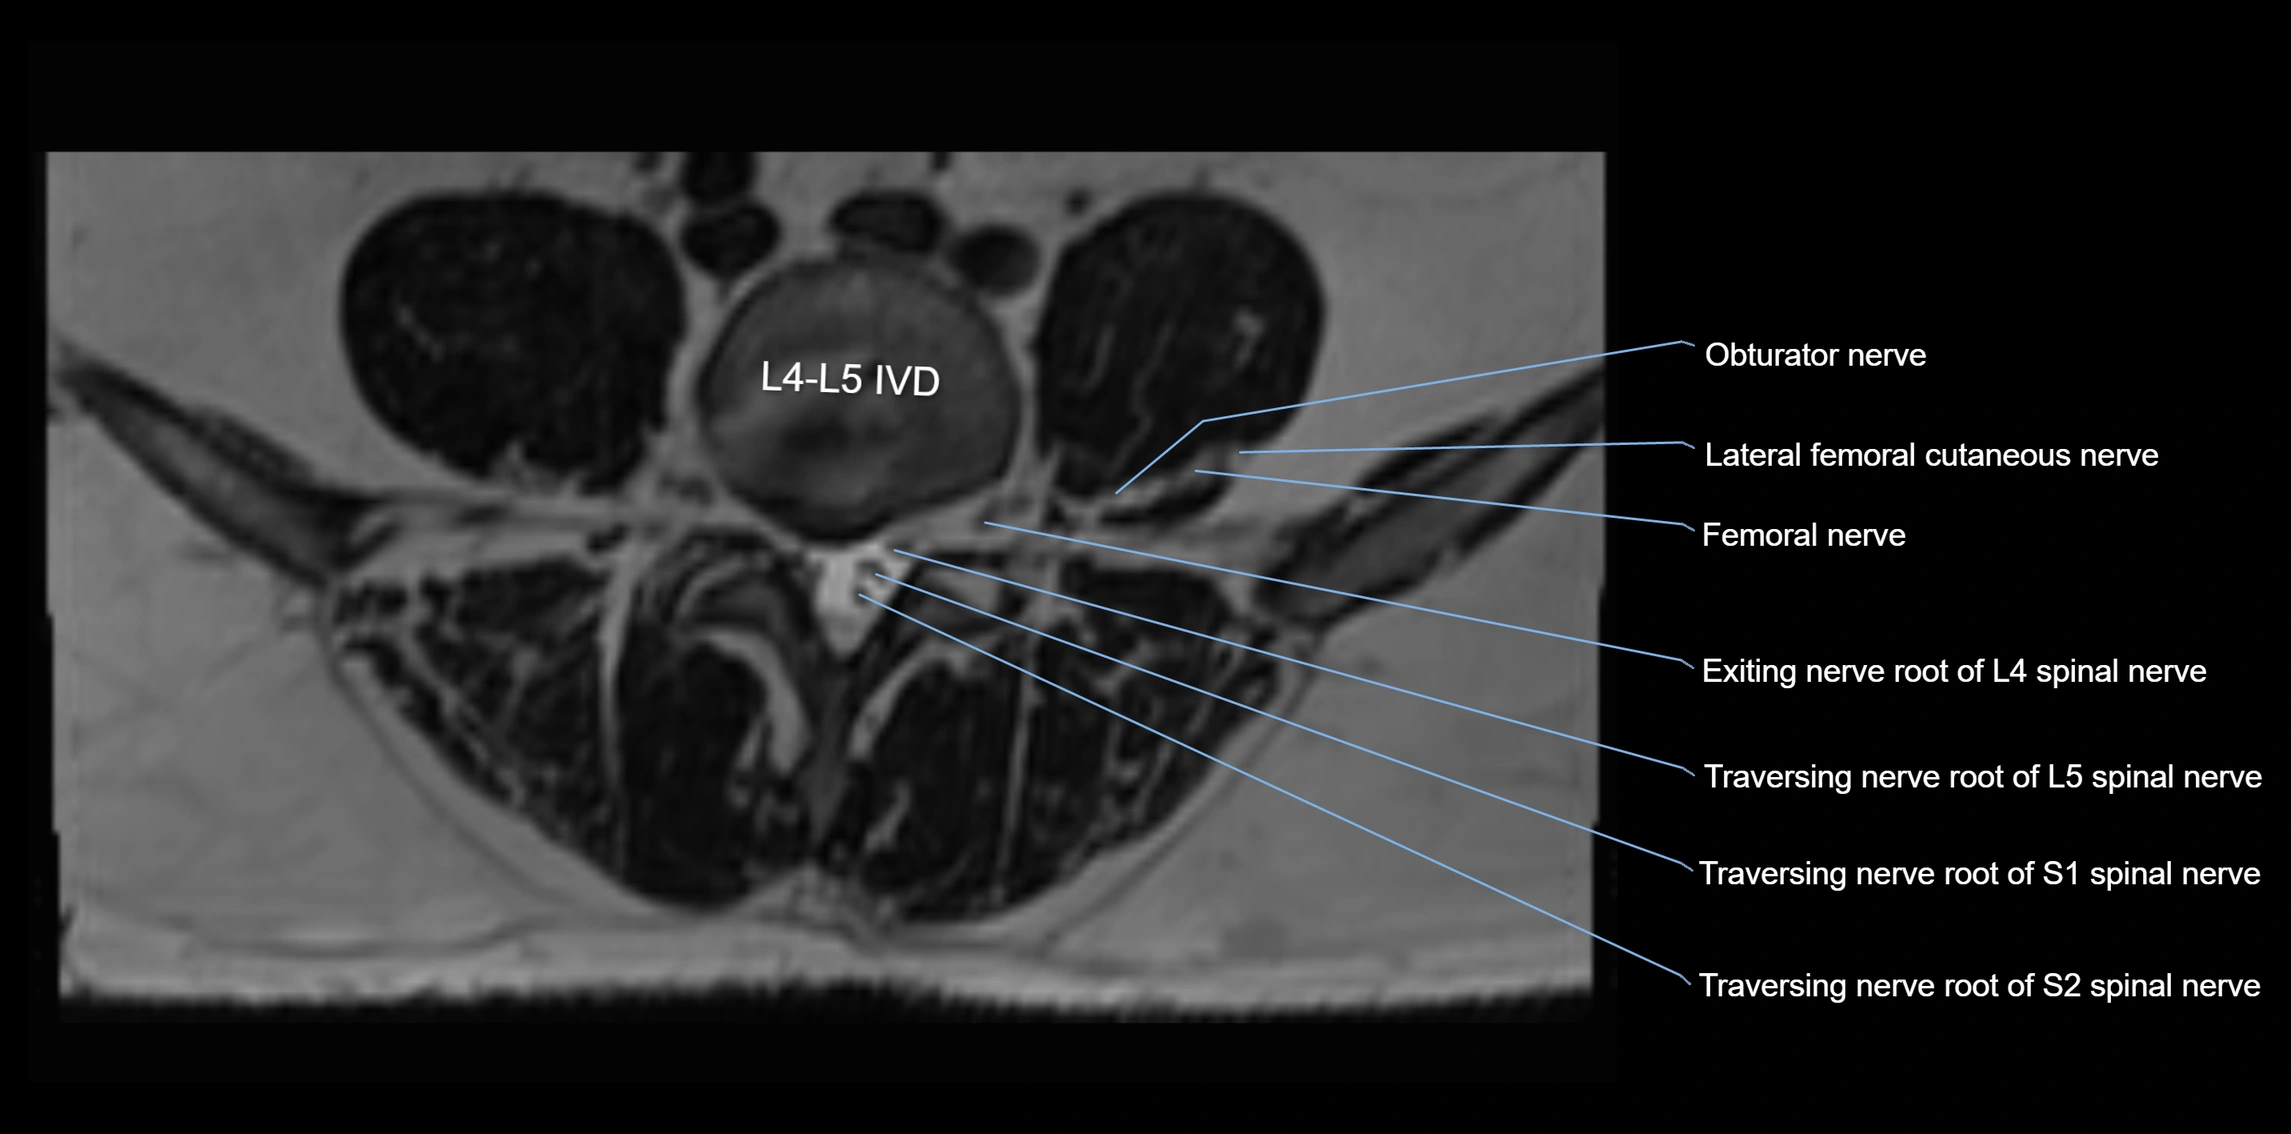

MRI image

image